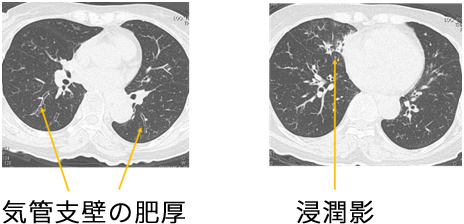

IgG4関連呼吸器疾患は、他の臓器の病変(対称性の涙腺・顎下腺病変や膵臓の病変など)を伴う事が多いため、それらの精密検査の最中に、胸部X線やCT検査にて、気管支の肥厚、浸潤影、腫瘤影などを指摘されて呼吸器科を受診する場合が多いです。またIgG4関連疾患は、アレルギー性鼻炎や気管支喘息などのアレルギー罹患歴が多いことも知られており、長引く咳や鼻汁などの症状で呼吸器科を受診することもあります。